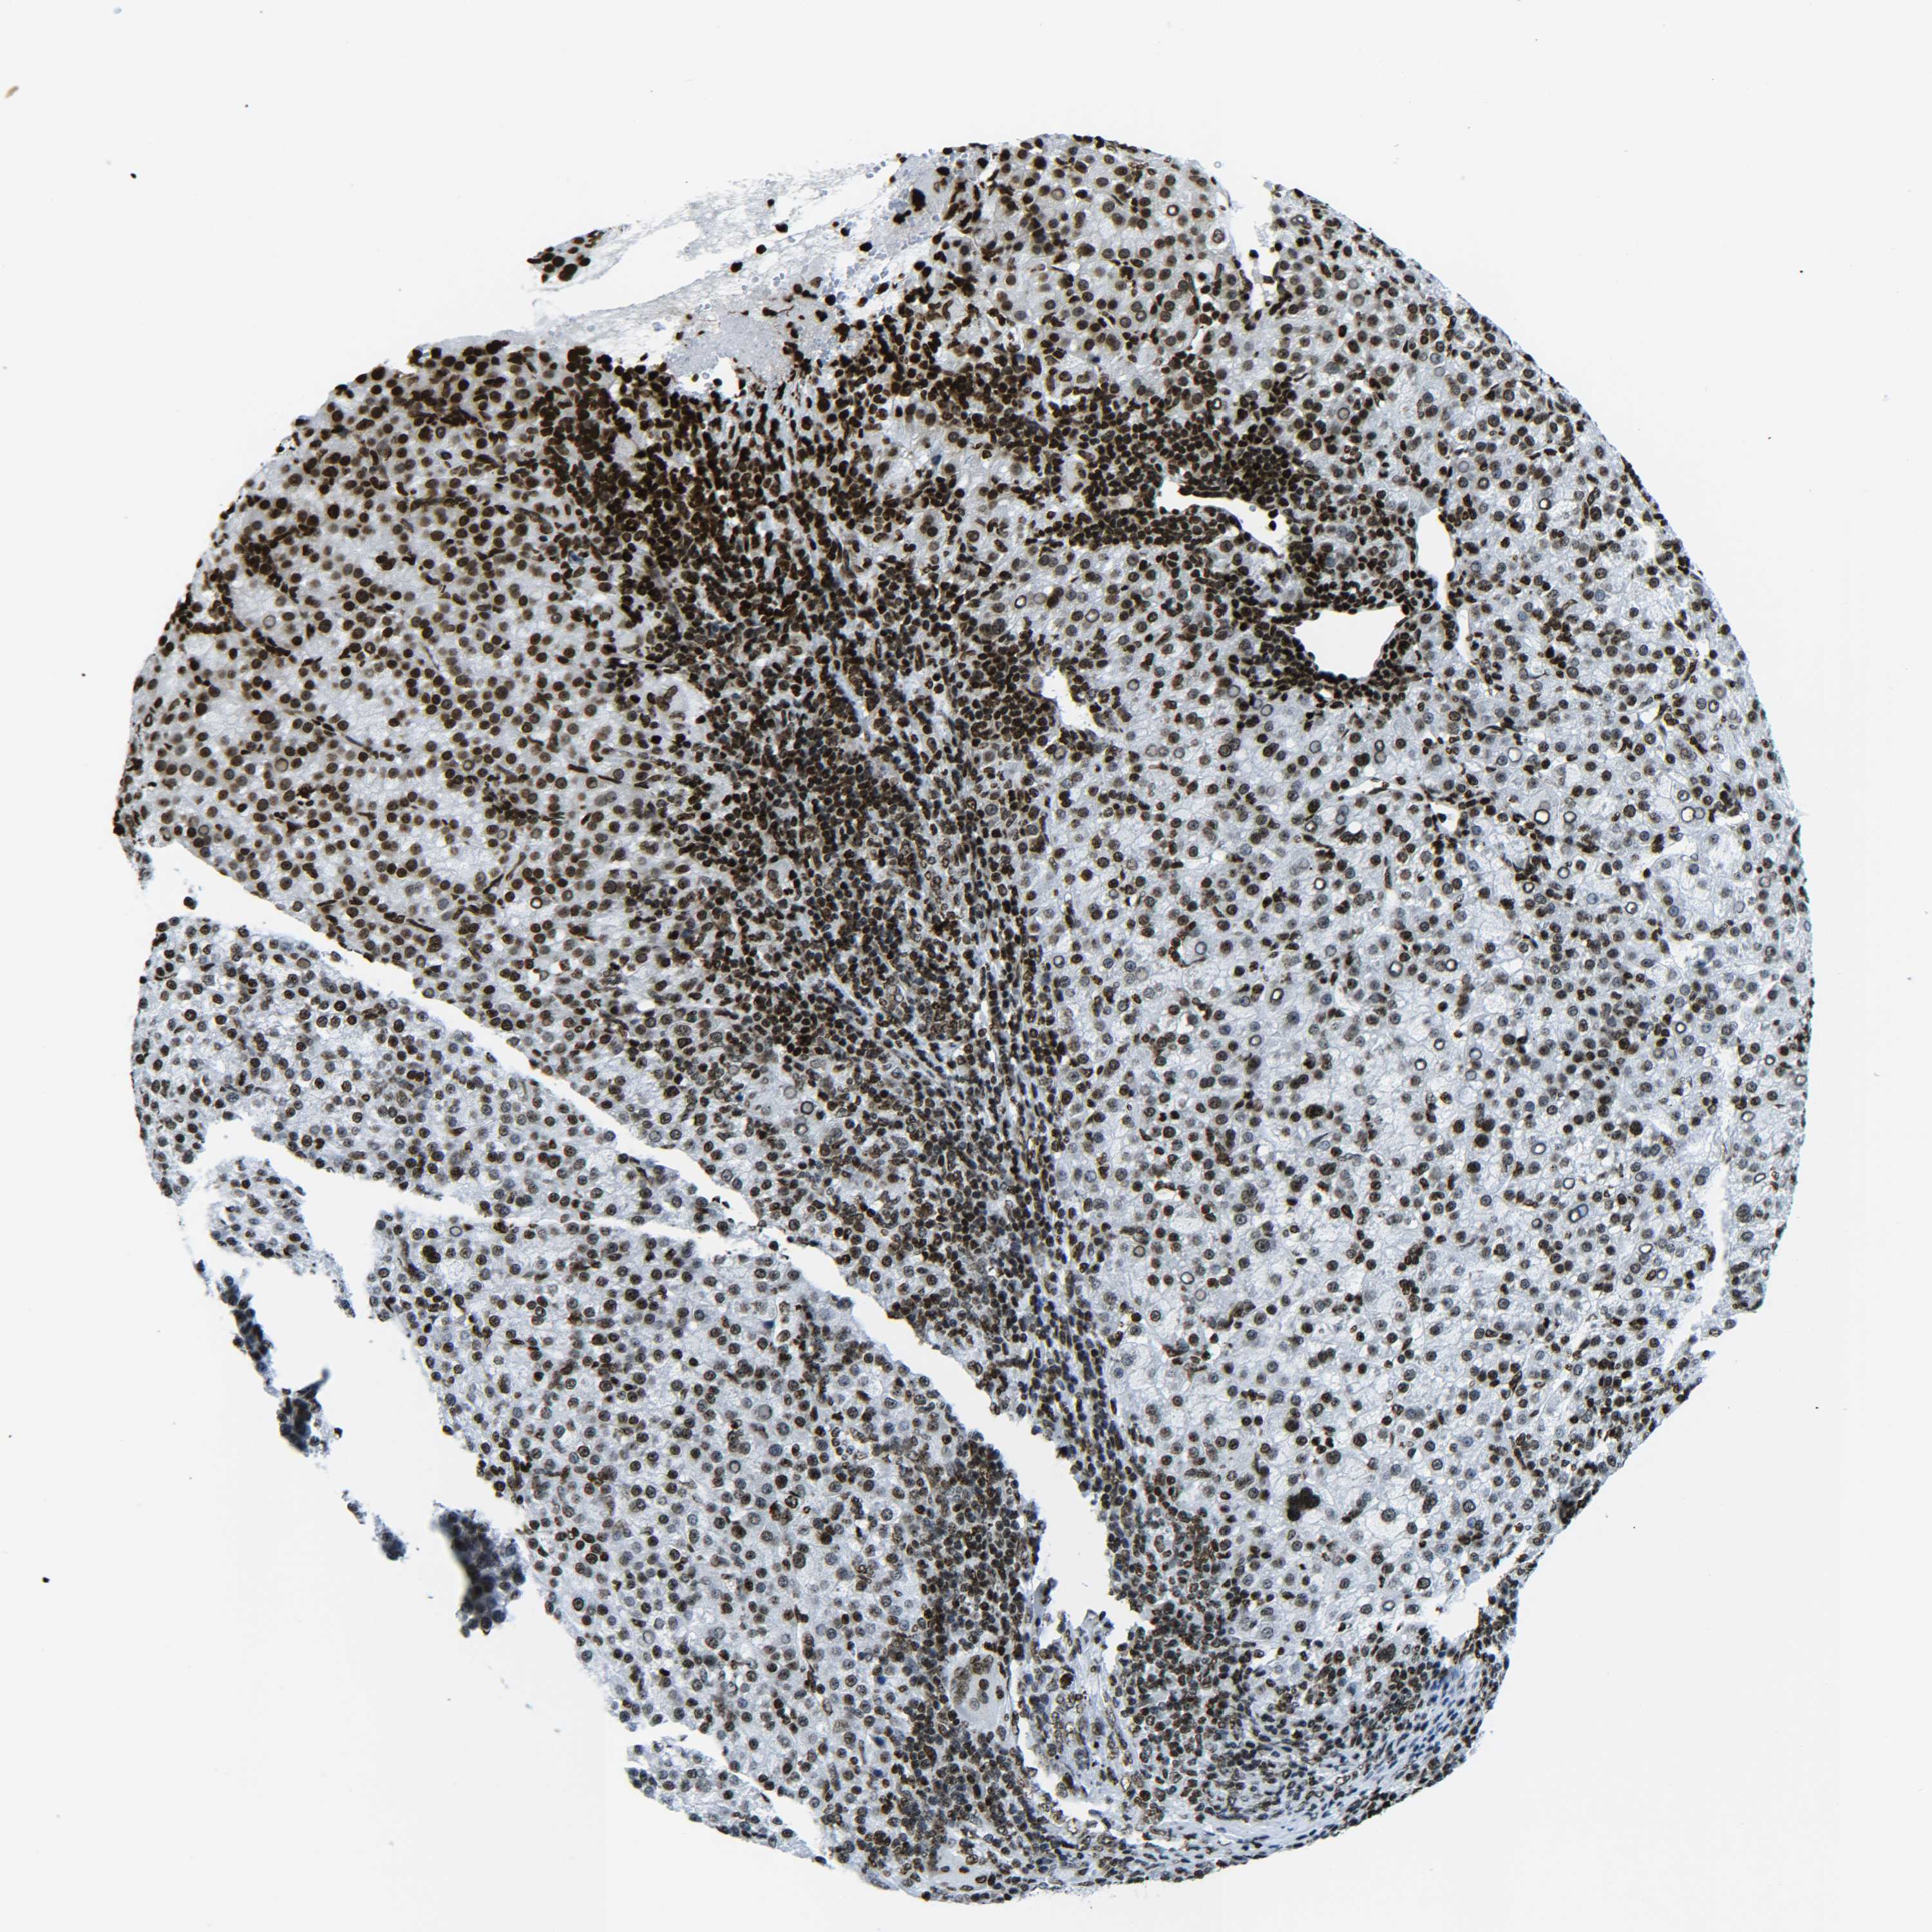

LIVER CANCER - Protein expressioni

A mouse-over function shows sample information and annotation data. Click on an image to view it in a full screen mode. Samples can be filtered based on level of antibody staining by selecting one or several of the following categories: high, medium, low and not detected. The assay and annotation is described here.

Note that samples used for immunohistochemistry by the Human Protein Atlas do not correspond to samples in the TCGA dataset.

Antibody stainingi

Antibody staining in the annotated cell types in the current human tissue is reported as not detected, low, medium, or high, based on conventional immunohistochemistry profiling in selected tissues. This score is based on the combination of the staining intensity and fraction of stained cells.

Each image is clickable and will lead to virtual microscopy that enables deeper exploration of all samples and also displays staining intensity scores, fraction scores and subcellular localization as well as patient and tissue information for each sample.

Antibody HPA041189

Antibody HPA051647

Antibody CAB012264

Staining

High

Medium

Low

Not detected

Intensity

Strong

Moderate

Weak

Negative

Quantity

>75%

75%-25%

<25%

None

Location

Nuclear

Cytoplasmic/membranous

Cytoplasmic/membranous,nuclear

Cholangiocarcinoma

Carcinoma, Hepatocellular, NOS